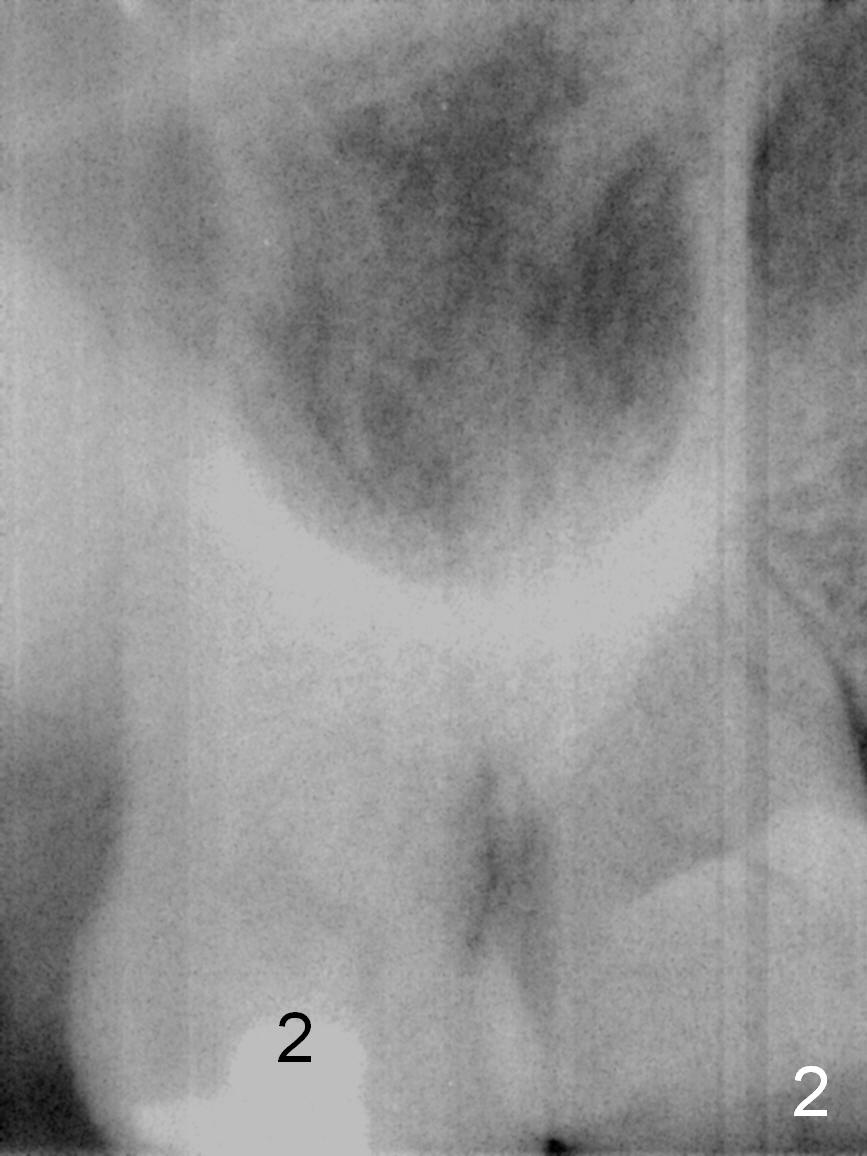

A 54-year-old woman has nocturnal pain at the tooth #2 (Fig.2), one year after extraction of the tooth #14 (Fig.1). A mesiodistal crack line is found at root canal therapy (Fig.3 arrowheads). The tooth appears to be nonsalvageable. The socket is either single or 3. Cut and soak 3 large pieces of gauze in Metronidazole. When the tooth is extracted, we will decide whether the gauze needs to be cut further. Depending upon the size of the septum, a relatively small (4.5x9 mm Fig.4) or large (6.5 mm) implant will be placed. The largest pair abutment will be installed to close the socket.